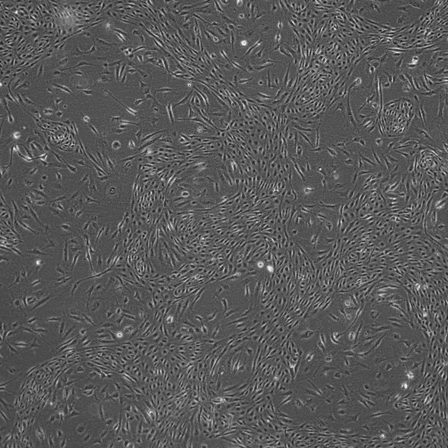

Endothelial cells are flat, thin cells that line the blood vessels and lymphatic system and are crucial in understanding vascular function, disease processes and tissue regeneration.

Endothelial cells can be differentiated from pluripotent stem cells using STEMCell Technologies protocols and media kits. The resultant cells are robust and reproducible cell models that can be used in biomedical research to investigate vascular health, disease mechanisms and potential therapies for a variety of conditions.